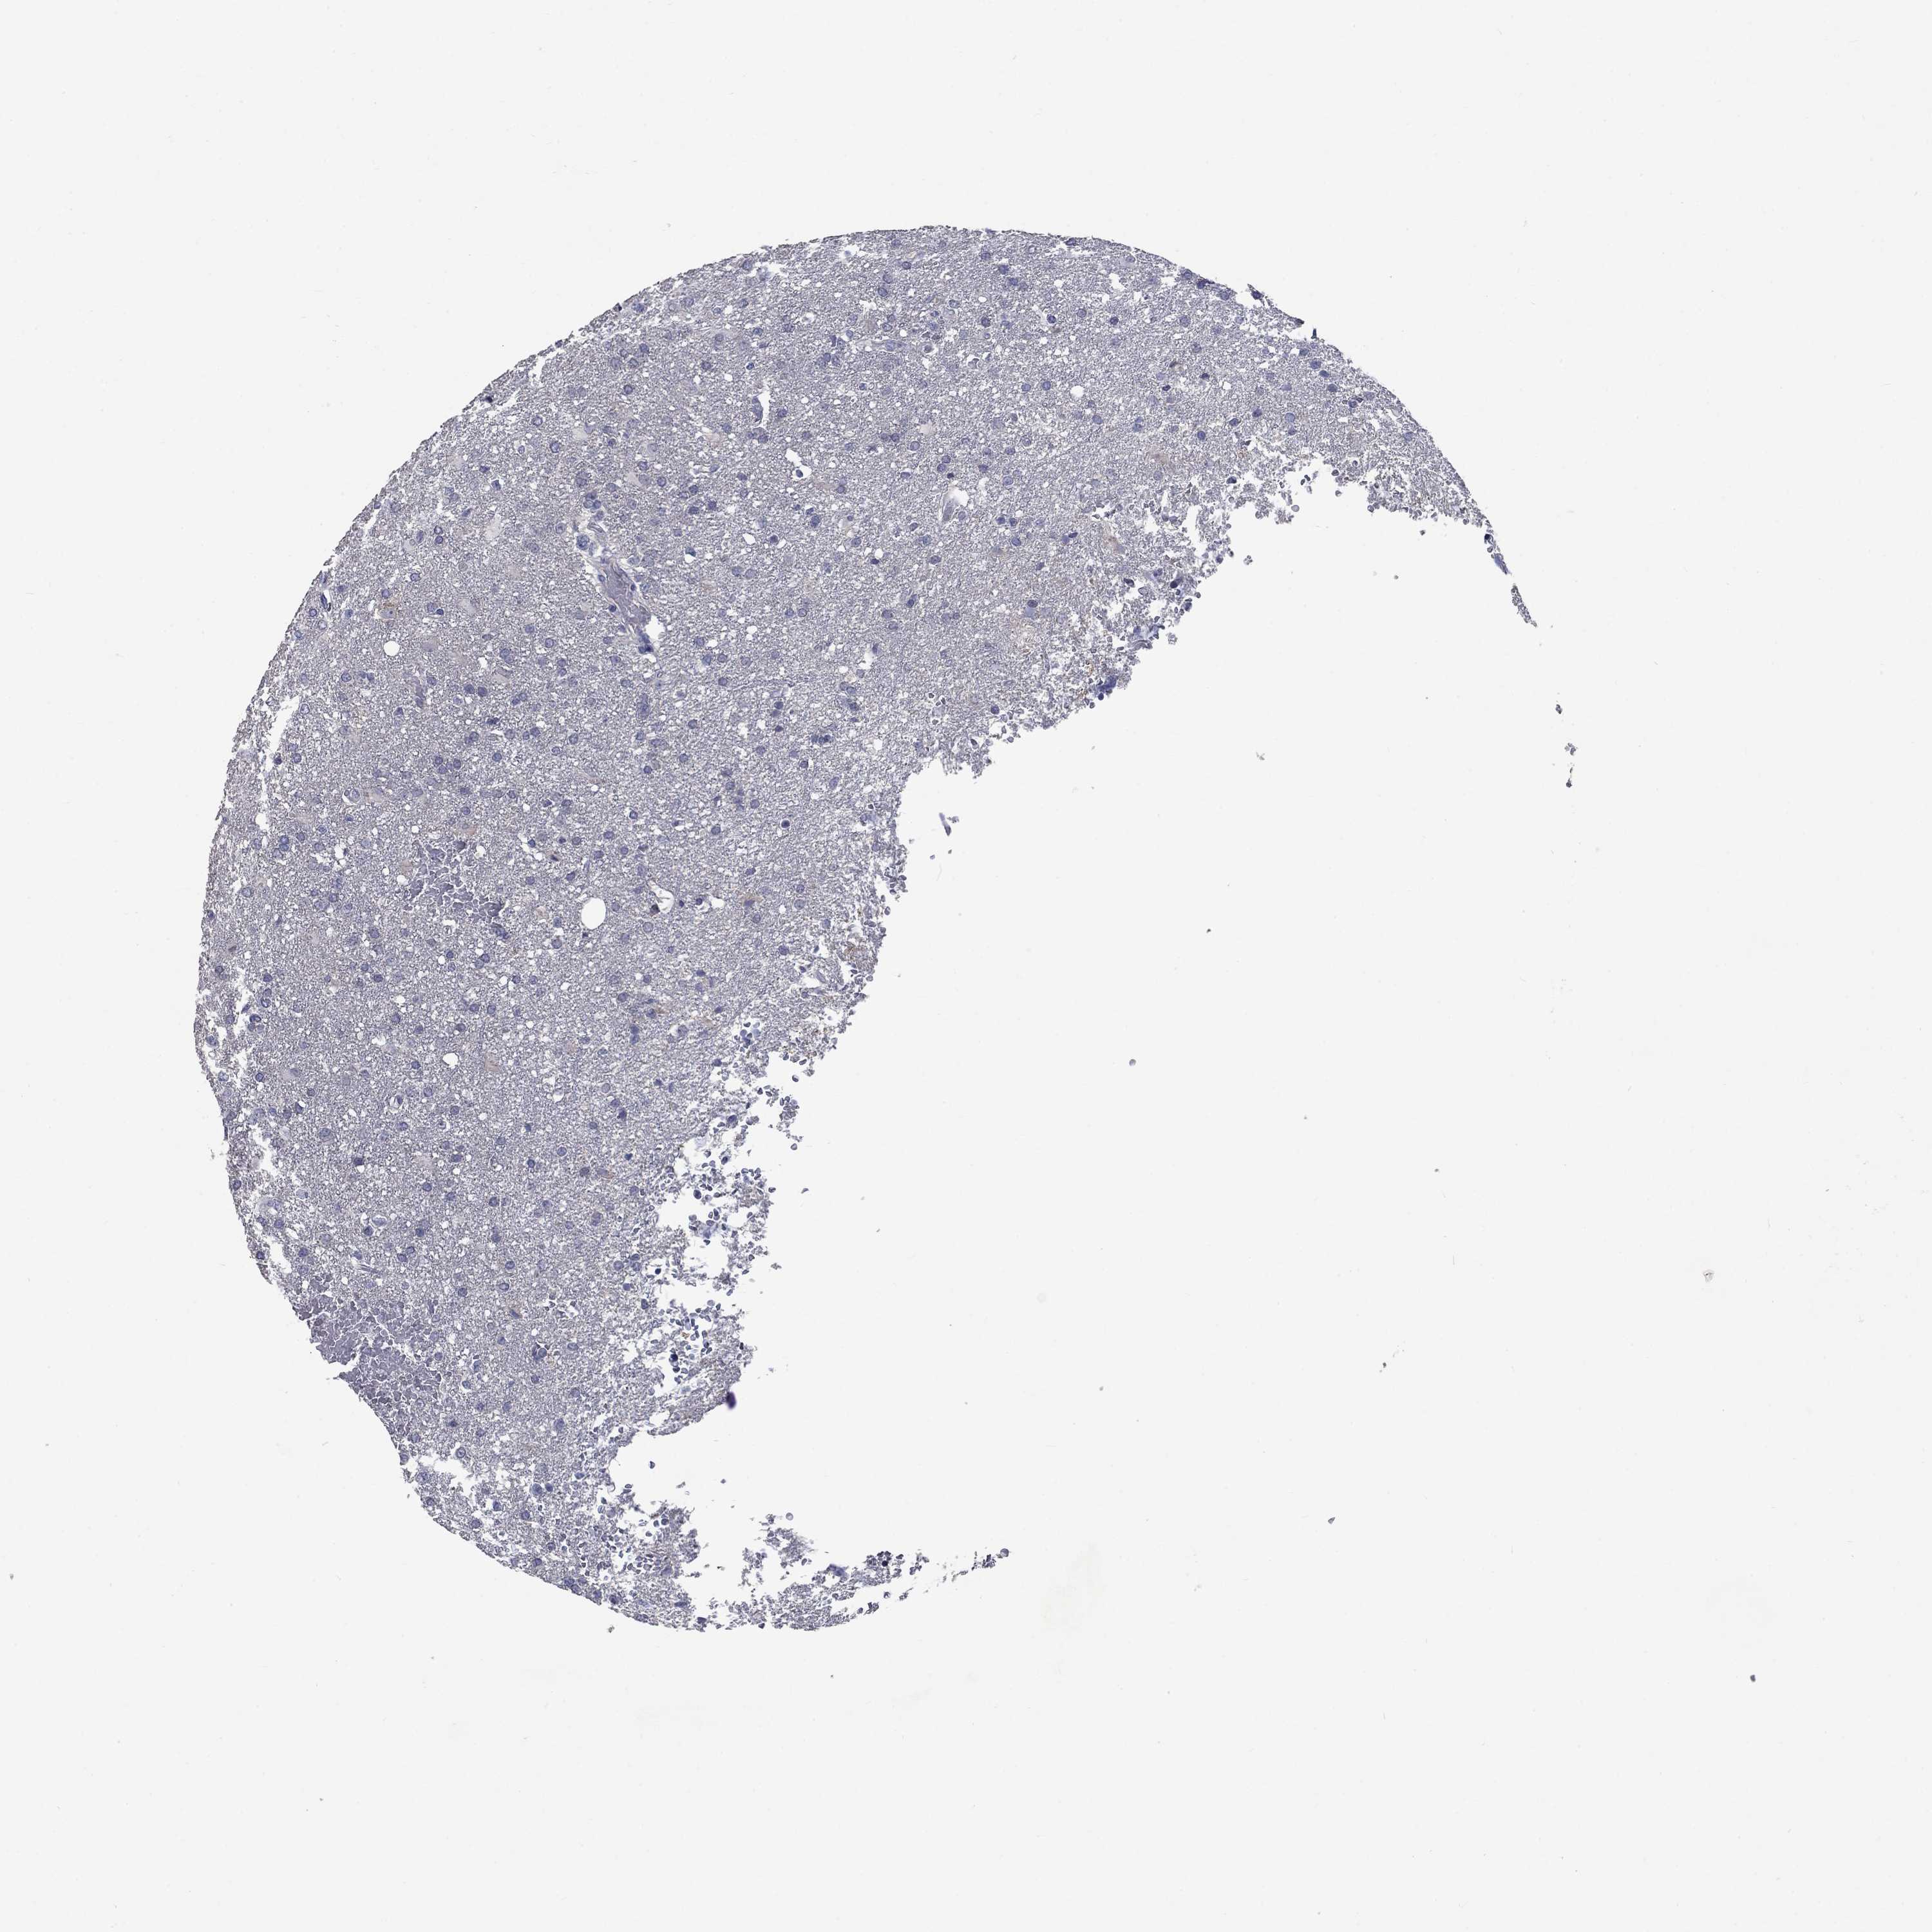

GLIOMA - Protein expressioni

A mouse-over function shows sample information and annotation data. Click on an image to view it in a full screen mode. Samples can be filtered based on level of antibody staining by selecting one or several of the following categories: high, medium, low and not detected. The assay and annotation is described here.

Note that samples used for immunohistochemistry by the Human Protein Atlas do not correspond to samples in the TCGA dataset.

Antibody stainingi

Antibody staining in the annotated cell types in the current human tissue is reported as not detected, low, medium, or high, based on conventional immunohistochemistry profiling in selected tissues. This score is based on the combination of the staining intensity and fraction of stained cells.

Each image is clickable and will lead to virtual microscopy that enables deeper exploration of all samples and also displays staining intensity scores, fraction scores and subcellular localization as well as patient and tissue information for each sample.

Antibody HPA068138

Antibody HPA071902

Glioma, malignant, Low grade

Glioma, malignant, High grade

Glioma, malignant, NOS